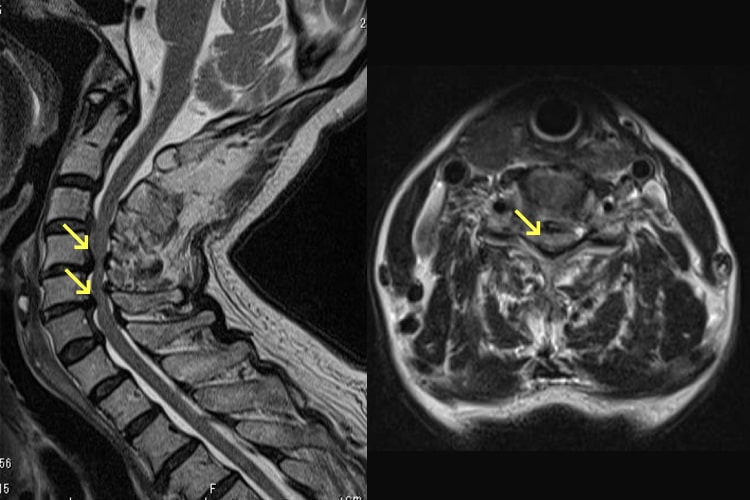

頚椎椎間板ヘルニア

頚椎椎間板ヘルニアとは、椎間板の一部が飛び出て神経を圧迫する病気です。20~30代の若い世代に多いといわれています。首や肩、腕に痛みやしびれが出たり(神経根の障害)、箸が使いにくくなったり、ボタンがかけづらくなったりします。また、足のもつれ、歩行障害が出ることもあります(脊髄の障害)。痛みが強い時期には、首の安静保持を心掛け、頸椎カラー装具を用いることもあります。また、消炎鎮痛剤や神経痛を抑える薬の服用で痛みをやわらげます。症状に応じて牽引療法を行ったり、運動療法を行ったりすることもあります。これらの方法で症状の改善がなく、上肢・下肢の筋力の低下が持続する場合、歩行障害・排尿障害などを伴う場合は手術的治療を選択することもあります。